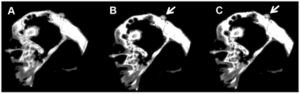

Presurgical Visualization of the Neurovascular Relationship in Trigeminal Neuralgia with 3D Modeling using Free Slicer Software

|

Publication: Acta Neurochir (Wien). 2016 Nov;158(11):2195-2201. PMID: 27543280 Authors: Han KW, Zhang DF, Chen JG, Hou LJ. Institution: Department of Neurosurgery, Shanghai Neurosurgical Institute, Changzheng Hospital, Shanghai, China. Background/Purpose: o explore whether segmentation and 3D modeling are more accurate in the preoperative detection of the neurovascular relationship (NVR) in patients with trigeminal neuralgia (TN) compared to MRI fast imaging employing steady-state acquisition (FIESTA). METHOD: Segmentation and 3D modeling using 3D Slicer were conducted for 40 patients undergoing MRI FIESTA and microsurgical vascular decompression (MVD). The NVR, as well as the offending vessel determined by MRI FIESTA and 3D Slicer, was reviewed and compared with intraoperative manifestations using SPSS. RESULTS: The k agreement between the MRI FIESTA and operation in determining the NVR was 0.232 and that between the 3D modeling and operation was 0.6333. There was no significant difference between these two procedures (χ2 = 8.09, P = 0.088). The k agreement between the MRI FIESTA and operation in determining the offending vessel was 0.373, and that between the 3D modeling and operation was 0.922. There were significant differences between two of them (χ2 = 82.01, P = 0.000). The sensitivity and specificity for MRI FIESTA in determining the NVR were 87.2 % and 100 %, respectively, and for 3D modeling were both 100 %. CONCLUSION: The segmentation and 3D modeling were more accurate than MRI FIESTA in preoperative verification of the NVR and offending vessel. This was consistent with surgical manifestations and was more helpful for the preoperative decision and surgical plan. |